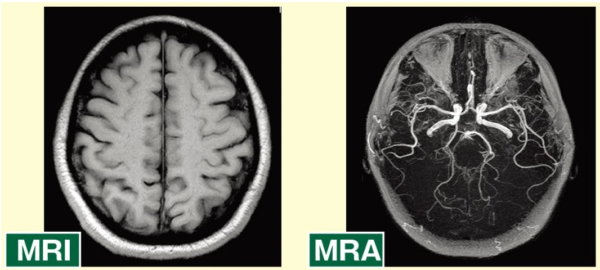

※ MRIとMRAの違い

- MRI(Magnetic Resonance Imaging):

脳の「全体像」や「組織そのもの」を見る(脳梗塞・腫瘍など)。 - MRA (Magnetic Resonance Angiography) :

「血管」に特化して見る(動脈瘤・狭窄など)。 - 同時に実施:

多くの脳ドックでは、一度の検査でMRIとMRAを同時に行い、脳の組織と血管の両方を包括的にチェックするのが一般的です。